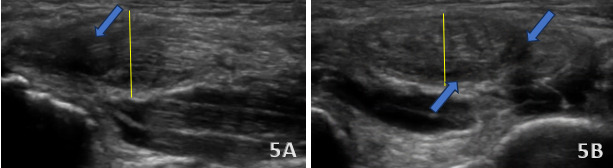

These two figures show a partial tear of the distal triceps brachii tendon (blue arrows). These tears typically present with a focal hypoechoic or anechoic area within the tendon, representing disrupted or absent tendon fibers. In a partial tear, some degree of fiber continuity remains, distinguishing it from a complete rupture. The long head may show localized fiber retraction or irregularity but with bridging fibers still visible across the tear site. In this case, shown above in Figures 5A and 5B, the tendon demonstrates diffuse thickening (yellow lines) and heterogeneous echotexture, consistent with chronic tendinosis. This often appears as hypoechoic areas interspersed with hyperechoic foci due to degenerative changes, mucoid degeneration, and possible calcifications. The tendon margins may appear poorly defined, and power Doppler imaging may reveal increased vascularity, indicating chronic inflammation or reactive hyperemia.